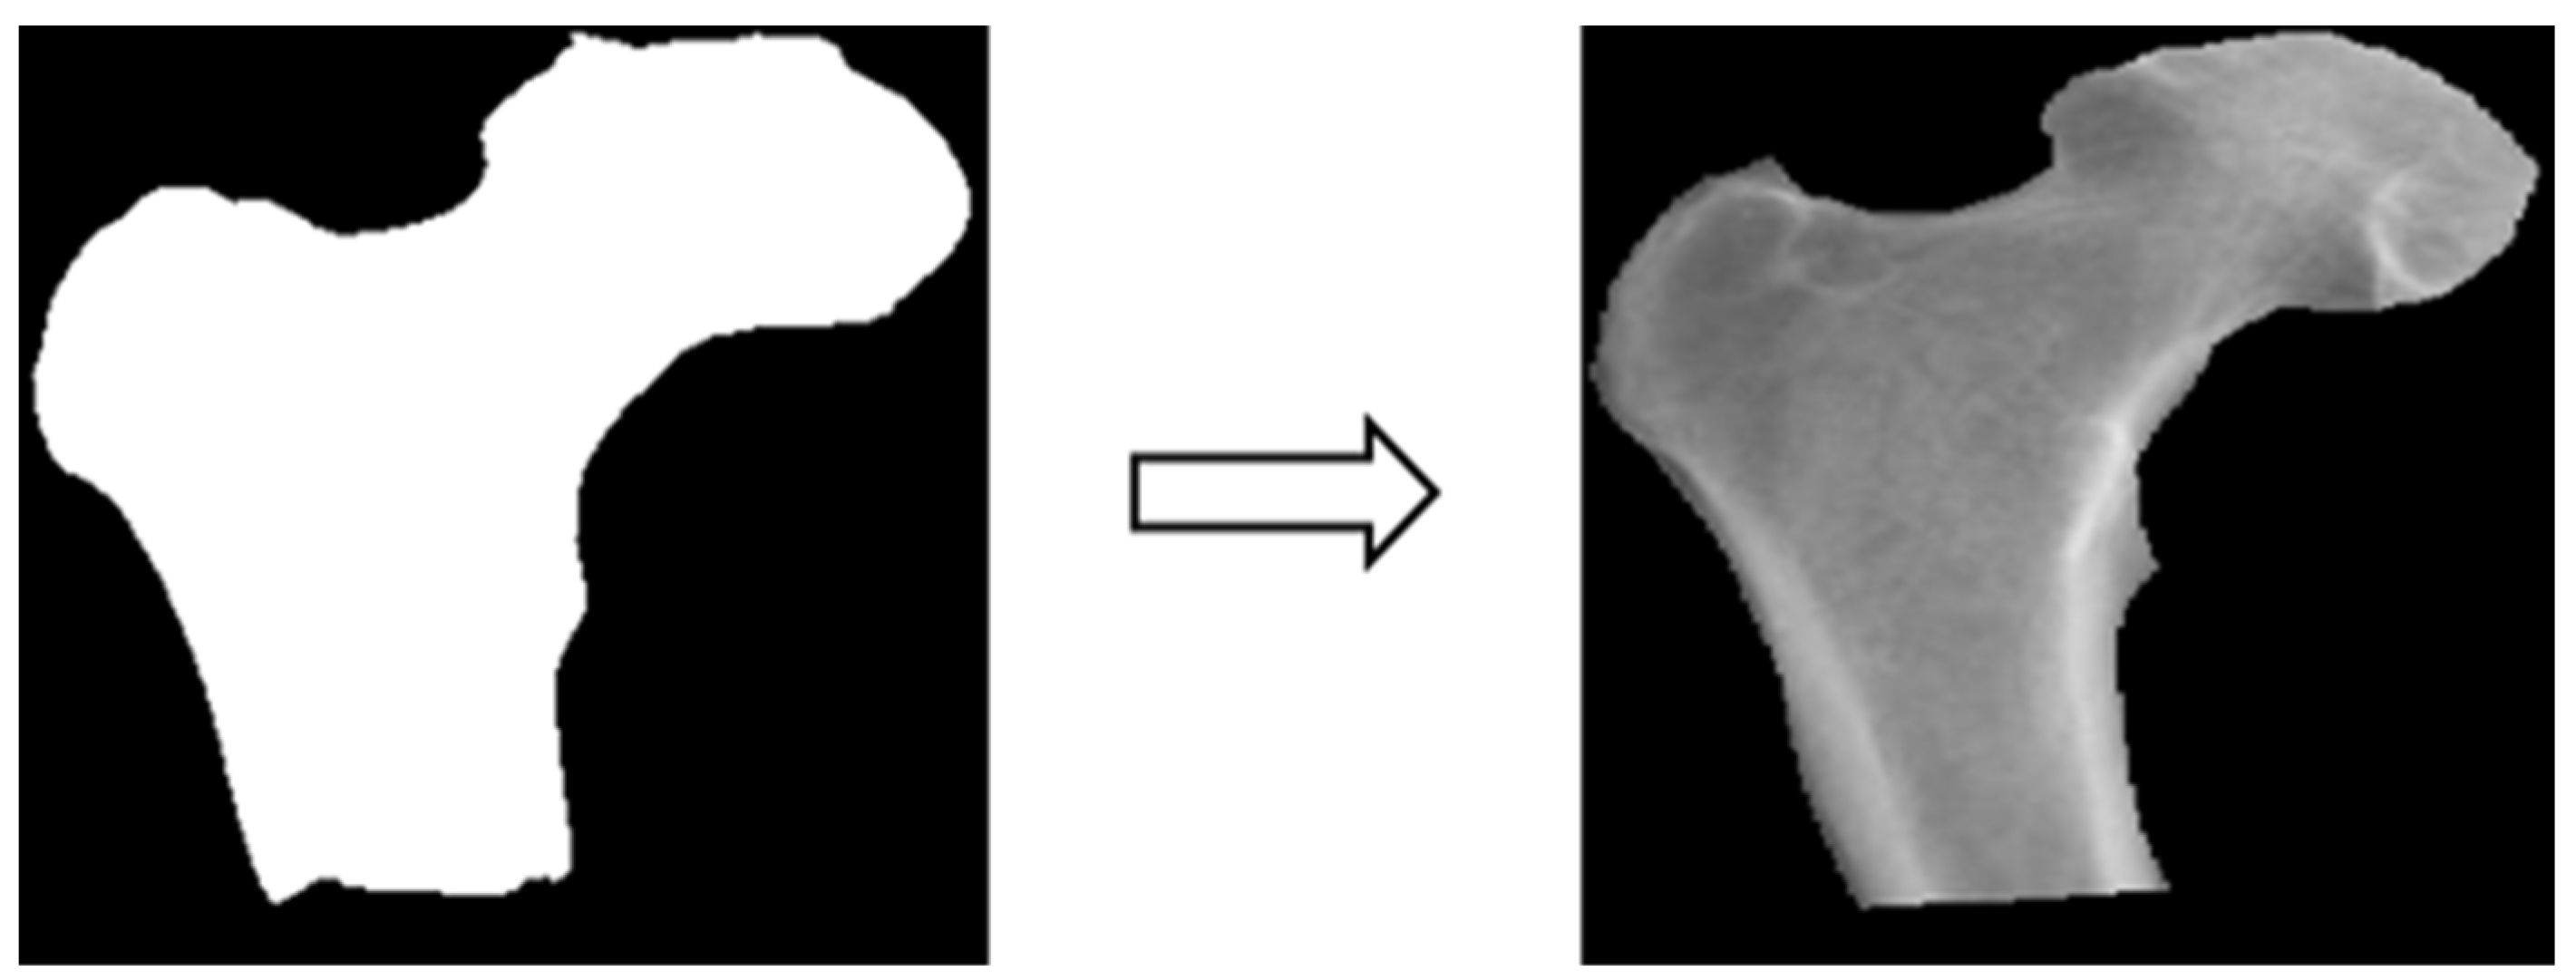

In this study, four parts of the image labeled X-ray images were used in image segmentation by feeding them into U-Net and U-Net++ models for training, and the bit depth of the four parts of the image was converted from the original 24 bits to 8 bits before the model training. The reason for choosing to use U-Net and U-Net++ is that their model structure is simpler, they do not need to spend a lot of time filtering out the remaining noise in the medical images, and they are less likely to form overfits for a small number of image datasets. The binary segmentation prediction results obtained after training the models of U-Net and U-Net++ are shown in Figure 3 below.

3.3.3. Image Matting

Based on the four parts of the image segmentation of the binary image and the original X-ray image together, the original X-ray image only retains the part of the image segmentation as shown in Figure 4; the other non-part of the contour of the background is removed, and the image is de-behind in the hope that it can enhance the accuracy of the classification of the depth of the learning process, and then the image classification will be segmented images and not segmented images will be compared.